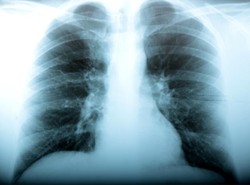

Co najmniej 6 250 osób zmarło na grypę A/H1N1, z czego 179 w ostatnim tygodniu - poinformowała Światowa Organizacja Zdrowia (WHO). Dane dotyczą 206 państw. "W Europie i Azji Środkowej nadal nasila się w całym regionie proces zakaźny w miarę, jak aktywność pandemiczna przesuwa się na wschód" - napisała WHO.

W Europie zmarło dotychczas "co najmniej 300" osób, czyli tyle samo co w poprzednim zestawieniu WHO z 6 listopada. W krajach Azji i Pacyfiku śmierć poniosły 1 194 osoby (wzrost o 35). Nowa grypa nadal najwięcej ofiar śmiertelnych spowodowała na kontynencie amerykańskim - 4 512 (wzrost o 113).